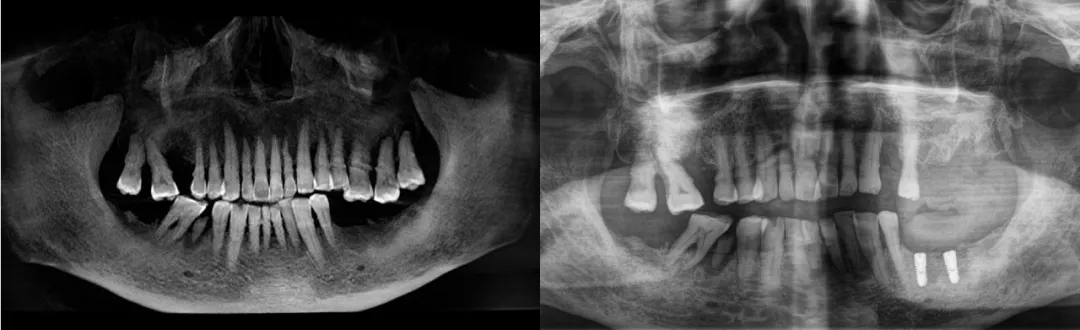

患者术前、术后对比

如今,做完种植牙的周爷爷笑容灿烂,曾经心心念念的螃蟹和猪脆骨也能轻松咀嚼了。对比种牙之前的生活,周爷爷后悔没有早点为自己做种植牙。